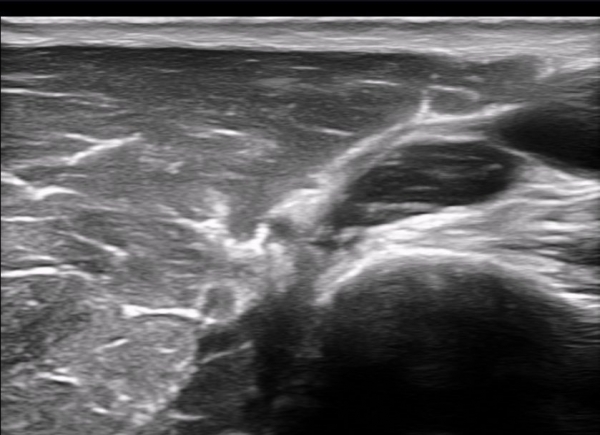

±ÙÀ°ÇǺνŰæÀÇ Á¾´Ü¸é°Ë»ç¿¡¼­ ±ÙÀ°ÇǺνŰæÀÇ ±¹¼ÒÀû ÇùÂø°ú ±ÙÀ§ºÎÀÇ Àú¿¡ÄÚ ºÎÁ¾ÀÌ °üÂûµÈ´Ù

(»çÁø 4, 5, 6,7) À̰ÍÀº ½Å°æÀÇ ¿°Àü(torsion)¿¡ ºÎÇÕÇÏ´Â ¼Ò°ßÀÌ´Ù.

½Å°æ º´º¯ÀÇ ÇǺο¡ Ç¥½Ã ÷ºÎÆÄÀÏ 5